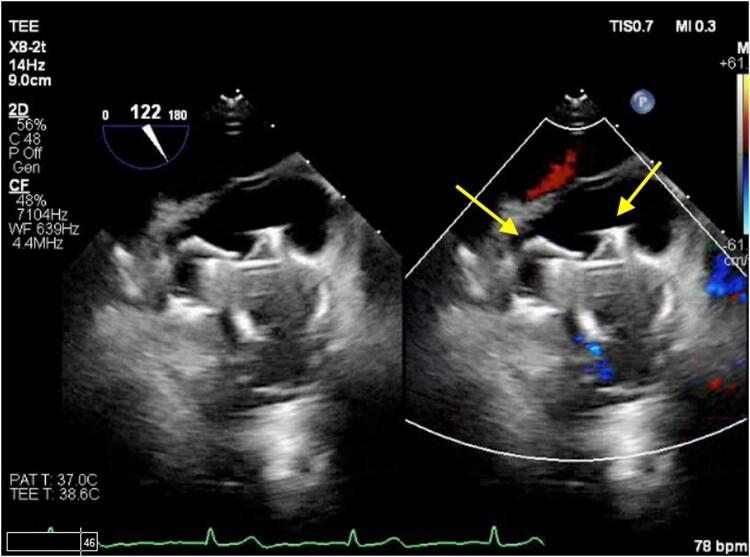

In this manuscript, we highlight the successful closure of a bilobed LAA with a large ostium utilizing two WATCHMAN™ FLX devices and using the double sheath technique. The aim was to achieve optimal closure and address the unique anatomical characteristics of the patient's LAA.

The utilization of two LAAO devices in bilobed appendage anatomy, where a single device may not be sufficient, is possible, although it poses a challenge because of the lack of technical expertise and limited published evidence. Transoesophageal imaging can serve as a valuable tool for assessing the precise anatomy of the LAA and guide the selection and placement of the occlusion devices.